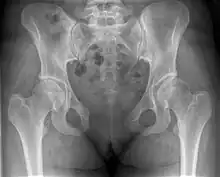

Pubic symphysis diastasis

| Post traumatic pubic symphysis diastasis | |

This abnormally wide gap can be diagnosed by radiologic studies such as X-ray, Ultrasound, MRI, CT scan or bone scan. While X-Ray is the gold standard to identify a separation of the pubic symphysis, a decision must be made in regard to which imaging modality to utilize that is patient and case-specific.[3]

X-ray

An X-ray film obtained in the AP view of the pelvic inlet and outlet will show a marked gap between the pubic bones.[3] A normal pelvis will show a gap that is 4–5 mm. However, in pregnancy the hormonal influences cause relaxation of the connecting ligaments and the bones separate up to 9 mm. A gap measuring greater than 10 mm indicates a pathological process.[3]

In addition, a view in the "flamingo stance" can be obtained to demonstrate the instability of the joint. This position consists of the patient standing with weight on one leg and the other bent.[6] A vertical displacement of more than 1 cm is an indicator of symphysis pubis instability.[7] A displacement of more than 2 cm usually indicates involvement of the sacroiliac joints.[3]